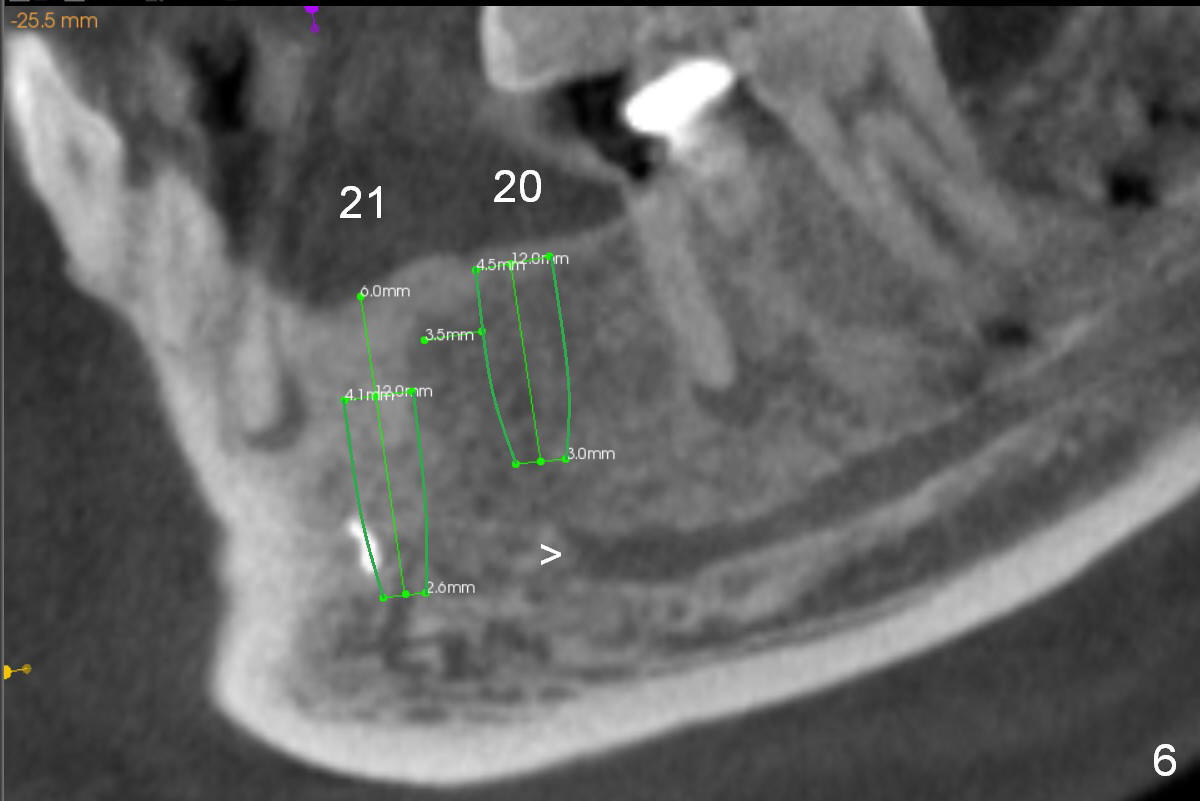

A 39-year-old man is pleased with implant placement at the lower right premolars (Fig.1: #28,29). He wants to have the same treatment at the lower left (#20,21), although the neighboring teeth need more urgent treatment. CBCT coronal sections at #21 (Fig.2) and 20 (Fig.4) show that the crest at the 1st premolar is particularly narrow and pointed. Since the Mental Foramen is at the 2nd premolar (arrowhead in Fig.4, 6 (sagittal section)), it seems appropriate to resect the atrophic crest by 6-7 mm at #21 (Fig.3 black area) and place a narrow implant low. It may invade the Incisive Nerve (Fig.7 brown cicle), which should be insignificant. A long abutment is expected at #21. A regular implant and abutment are expected at the 2nd premolar, similar to the right side. Smaller implants may be more appropriate (3.8 mm) to reduce postop bone resorption. In fact, the patient cracks the tooth #31. It seems to be nonsalvageable. In fact, what is to be done?